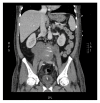

Case presentation: Herein we report the first case of C. burnetii infection presenting as an isolated retroperitoneal mass. A 61-year-old male underwent axillary-bifemoral bypass surgery. His postoperative course was complicated by the discovery of a large retroperitoneal mass.